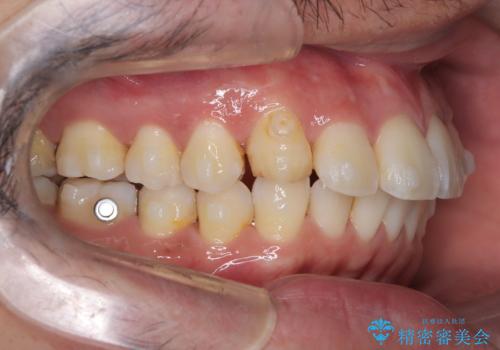

【インビザライン】前歯の凸凹を解消。

- 前歯の凸凹を主訴に来院されました。

もともと、顎が左にシフトしていたので正中が合わないことを説明した後、矯正を開始しています。

短期間で前歯のがたがたがきれいになり、満足していただけました。